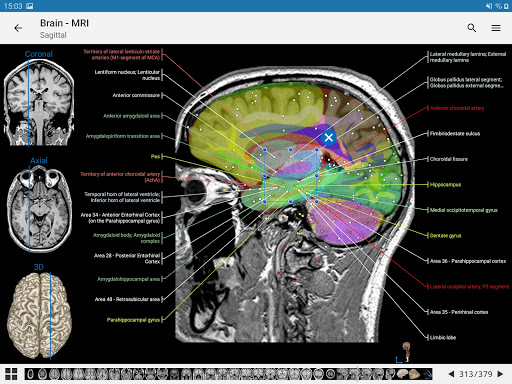

*Find your anatomical parts more easily thanks to the new, more intuitive and powerful search feature

*Improved visibility of anatomical parts definitions

*Browse between anatomical parts using description links

- “Filter by”, in the details view you can now filter the images containing the anatomical structure by modality

- “Filter by”, in the details view you can now filter the images containing the anatomical structure by modality